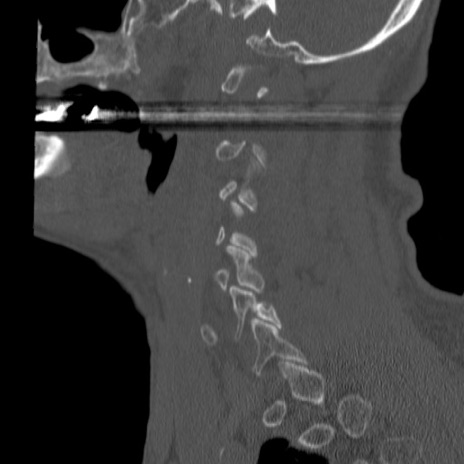

症例46 頚椎CT(矢状断像)

【症例】80歳代男性

【主訴】両側頚部〜上肢のしびれ

【現病歴】昨日、自宅内で転倒、その後より上記症状あり。意識障害なし。

【身体所見】両側上肢のallodynia(熱痛覚過敏)あり。MMTおよびDTRは正確な所見取れず。両上肢の挙上はなんとか可能。

異常所見と診断は?